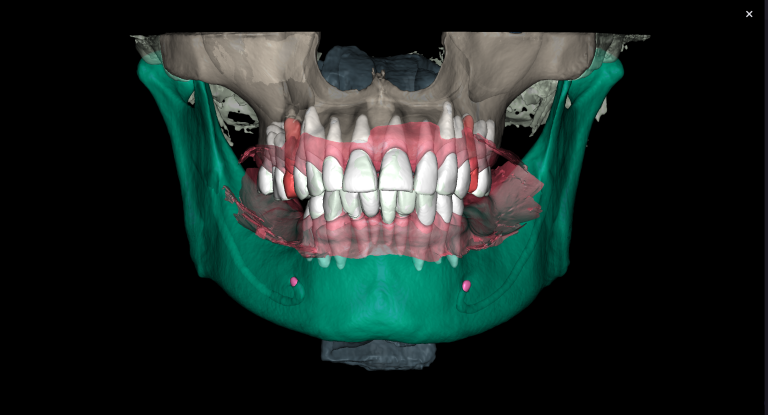

To plan implant treatment for the replacement of tooth 25 (Universal 13), the intraoral scanning data was uploaded into the STL module and obtain a 3D model for selecting the optimal spatial position of the implant and planning the virtual design of the template

Fully automatic segmentation and creation of 3D models from DICOM files allows you to select individual structures for printing models on a 3D printer